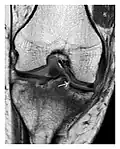

Figure 9: Proximal metaphyseal fatigue fracture of the tibia in a 27-year-old recent male military recruit. (a) Anteroposterior radiograph is within normal limits. (b) Coronal T1-weighted MR image shows a marked linear hypoattenuation along the medial tibial metaphysis (arrow) surrounded by diffuse hypointensity in keeping with posttraumatic edema.[1]

Figure 8: Proximal diaphyseal fatigue fracture of the tibia in a 20-year-old man with a history of regular jogging. (a) Lateral radiograph shows no obvious fracture lines but a subtle localized medial tibial cortex periosteal reaction (arrows). (b) Sagittal reformatted CT image acquired 1-month after the radiograph shows a linear hypoattenuation in the tibial cortex (arrowhead), as well as obvious periosteal thickening (arrows). (c) Sagittal T2-weighted fat-saturated image acquired the same day shows an area of hyperintensity spreading over the proximal tibia (arrows), which is consistent with the presence of proximal tibial fracture.[1]